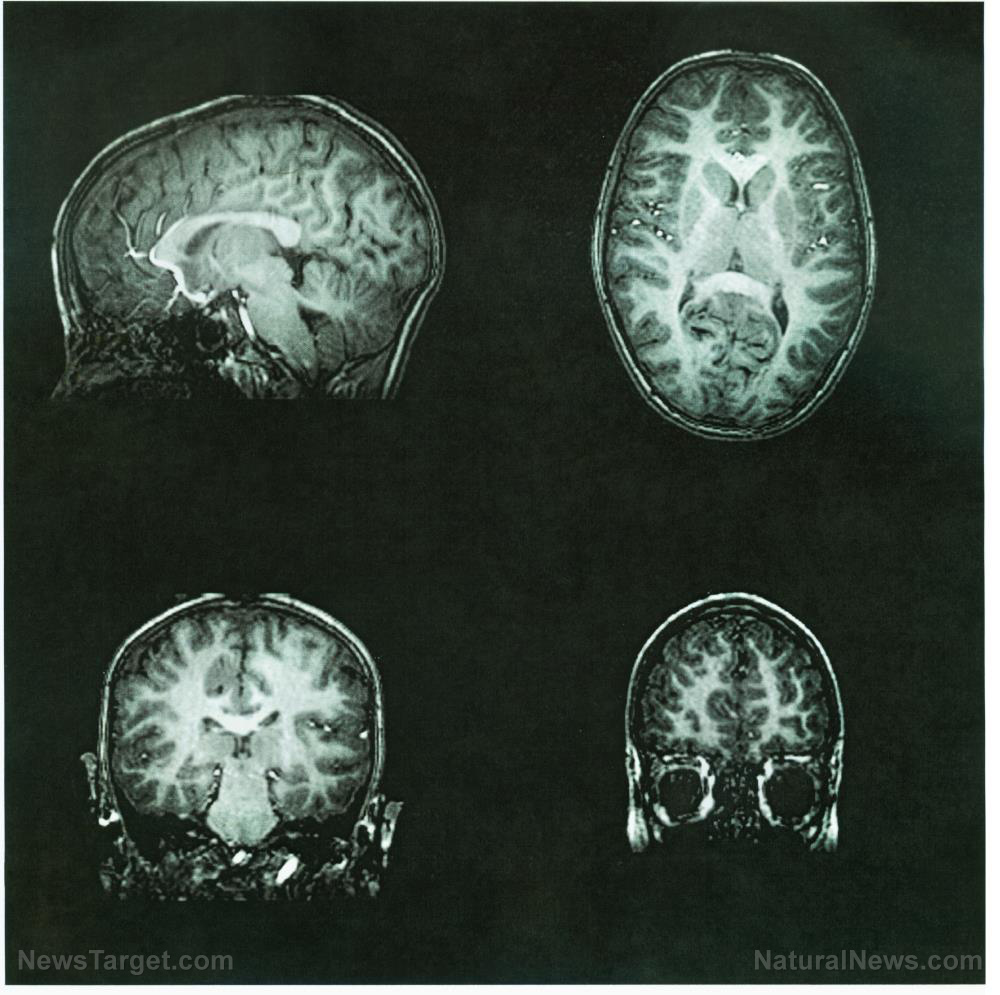

Neurological damage linked to Alzheimer's may be repaired with dietary supplementation

Is it really possible to mitigate and even reverse the damaging effects of Alzheimer's disease and dementia through simple dietary supplementation? According to new research out of Denmark, it certainly is. Professor Vilhelm Bohr and an international team of scientists hailing from the Center for Healthy Aging at the University of Copenhagen and the American National Institute of Health found that nicotinamide adenine dinucleotide, also known as NAD+, helps to clear up congestion of tau proteins in nerve cells and minimize DNA damage, among other benefits. Using a mouse model that mimicked the features of Alzheimer's disease in humans, Prof. Bohr and his colleagues added a substance to the rodents' drinking water that stimulated increased production of NAD+ in their cells. Those mice that received the supplement, resulting in increased NAD+ levels inside their bodies, experienced improvements in various markers associated with brain health. These included improvements in the activity and reorganization of the mice's brain cells, as well as increased production of new nerve cells from stem cells. The supplement also resulted in less damage to and fewer dead nerve cells. "Our study shows that the brains of the mice during the three-month period where they received the compound showed fewer of the characteristics associated with Alzheimer's disease," Prof. Bohr reported about his team's findings, noting that the supplement both prevented and removed existing damage to DNA in the hippocampus regions of the mice's brains. "In several behavioural and memory tests the mice received higher scores than mice who had not been given the supplement." For more related news about dietary supplementation the many ways that it can help improve human health, be sure to check out AlternativeMedicine.news.